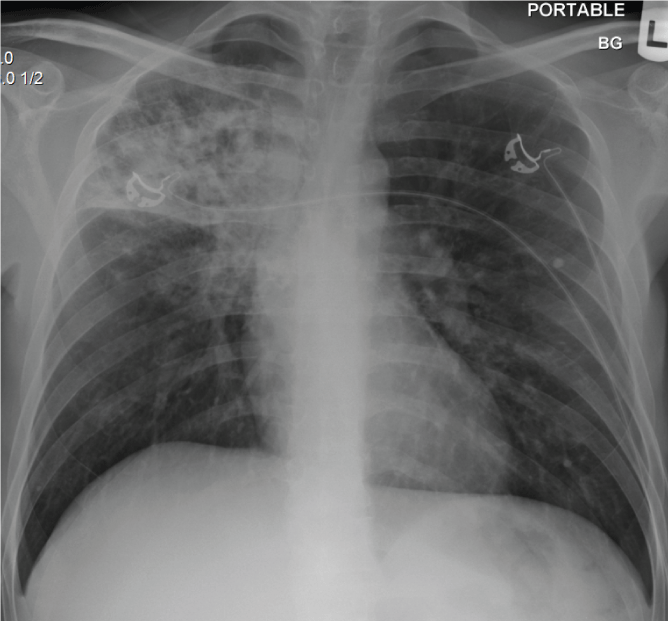

A young 32 year old Hispanic man presented with 4-weeks history of polyuria, polyphagia and weight loss and 2-weeks history of hemoptysis and shortness of breath. He denied fever, chills, night sweats, sick contacts, skin rash, glandular swelling or recent travel. He was a farmer who had emigrated from Mexico to New York City over a year ago and was currently working at a local grocery store. He denied any prior history of pulmonary symptoms. On examination the patient was cachectic, febrile, tachycardic and tachypneic and in respiratory distress. There were bronchial breath sounds in the right infraclavicular area. Laboratory investigations revealed mild leukocytosis and diabetic ketoacidosis (DKA). The chest X-ray (Figure 1) showed a dense right upper lobe infiltrate with bronchiectasis. A chest computed tomography (CT) (Figure 2) showed cavitary consolidation of the right upper lobe with patchy infiltrates in the right and left lower lobes.

Figure 1: Chest radiograph showing right upper lobe consolidation and

retraction of horizntal fissure.

Figure 2: (A) Representative image of Chest CT showing dense consolidation

of the right upper lobe. (B) Represenattive image of Chest CT showing

bilateral patchy lower lobe infiltrates.